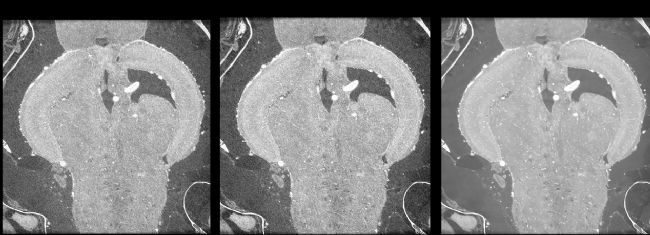

全新DeepRecon Pro ImageClarity™通過深度學習算法,在降噪的同時完整保留關鍵特征。無論是微納米級結構,還是材料內部缺陷,細微特征纖毫畢現。

斑馬魚腦實測結果展示

內置「圖像差異對比」功能,一鍵切換比對標準重建與AI優化結果,確保去噪不丟細節,讓每一份數據都經得起推敲。

(a) 標準圖像;(b) DeepRecon Pro ImageClarity 圖像;(c) 測試:使用正確模型去除噪聲;(d) 去除特征:選擇了不正確的模型。